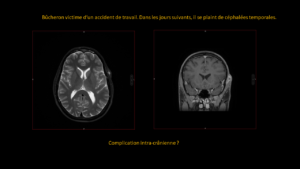

Deux mois après une entorse, persistance d’une importante douleur à la marche.

A droite pour comparaison, une radiographie de cheville qui est normale.

A gauche, le cheville du patient…quel est votre diagnostic?

RÉPONSE

Sur la radiographie simple, il est très difficile de visualiser la problématique.

La persistance de la douleur impose de réaliser une IRM qui révèle alors une fracture du calcanéum.